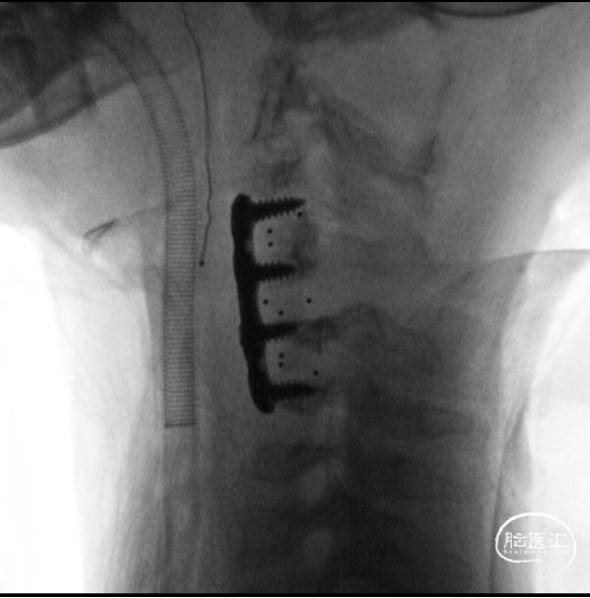

C3-4,C4-5,C5-6融合器放置完成

上钢板及螺钉,显示C5椎体无法良好复位

C5复位后置换置入前路螺钉